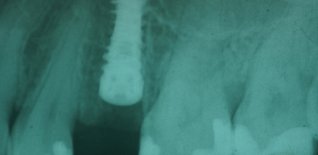

Dopo l'estrazione viene eseguito l'impianto e l'elemento dentario immediato.